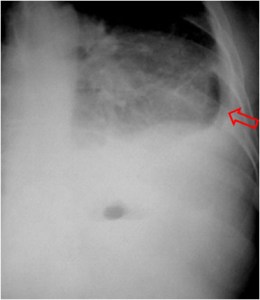

Estos esquemas permiten entender el significado del signo. Las colecciones intrapulmonares (izquierda) suelen tener una morfología redondeada, ya que están rodeadas por entero de pulmón y la resistencia de este al crecimiento de la colección es igual en todos sus puntos. Por ello, en las dos proyecciones los bordes superiores de la cavidad -delimitados por el aire que contiene la misma- son perpendiculares a la incidencia del rayo, y por tanto son visibles.

Las colecciones extrapulmonares (derecha) tienen a crecer limitadas por la pleura, que ofrece resistencia al crecimiento de la colección. Así, estas colecciones tienen una forma alargada (en «huso») a lo largo del espacio extrapulmonar. Por ello, en al menos una de las proyecciones, los bordes de la cavidad no son perperdiculares a la incidencia del rayo, y por tanto no son visibles. Como muestra el esquema, las colecciones posteriores (y también las anteriores, se ven bien en la proyección lateral y falta la pared superior en la proyección PA. Con las colecciones laterales ocurre lo contrario.